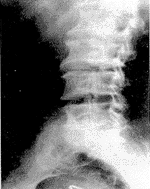

(1)椎小关节增生肥大:表现为关节突增大,关节面变形,关节间隙变窄,本组14例,34个关节面,其中侧隐窝狭窄13个关节。骨赘形成:可见关节边缘有均质硬化赘生物形成8例,16个关节面。腰椎关节突关节位片表现为椎小关节面密度增高伴关节间隙狭窄有12例,28个关节面(图1)。

图1 腰椎关节突关节位见L1/L2、L2/L3椎小关节间隙狭窄、关节面骨质硬化